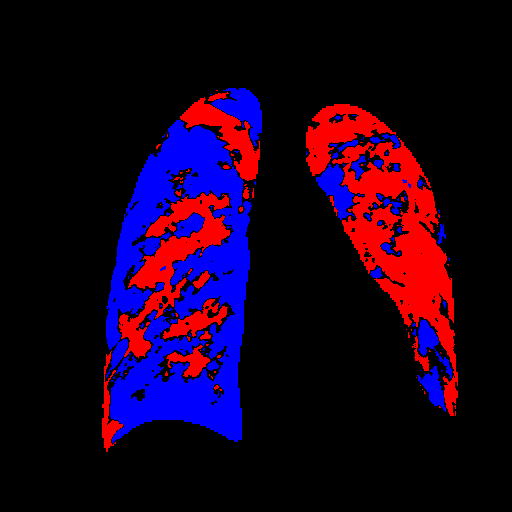

We therefore illustratively test our model in regard to its latent capability to induce disease in specific locations through the simple expedient of conditioning on positionally-indicative text. The results may be seen in figure 7 for the case of localized lung opacity (lung opacity being chosen because it is both diffuse and generally specific to one or other lung). The respective condition texts are “large lung opacity on the left” and “large lung opacity on the right”.